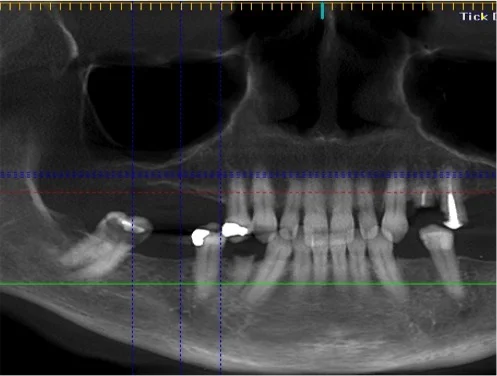

Immediate loading of implants with hybrid prostheses may be beneficial for patients with failing dentition. The success of computer-based planning of implant position and production of stereo-lithographic surgical templates has also been demonstrated. Alternatively, 3D stereo-lithographic models may be used for implant treatment planning, however long-term data has not yet been reported. The aim of this non-interventional, retrospective case series was to evaluate the outcome of immediately loaded implants in patients with failing dentitions that require bone tablingusing a bone reduction guide and a surgical guide manufactured directly on 3D models.

The standard three- to six-month healing time for implants is no longer an absolute. In selected cases, it is now possible to load the implants in fewer than two months; and, in some cases, immediate loading is possible. This article contains a case study showing that with careful patient selection, immediate loading appears to be an acceptable technique.